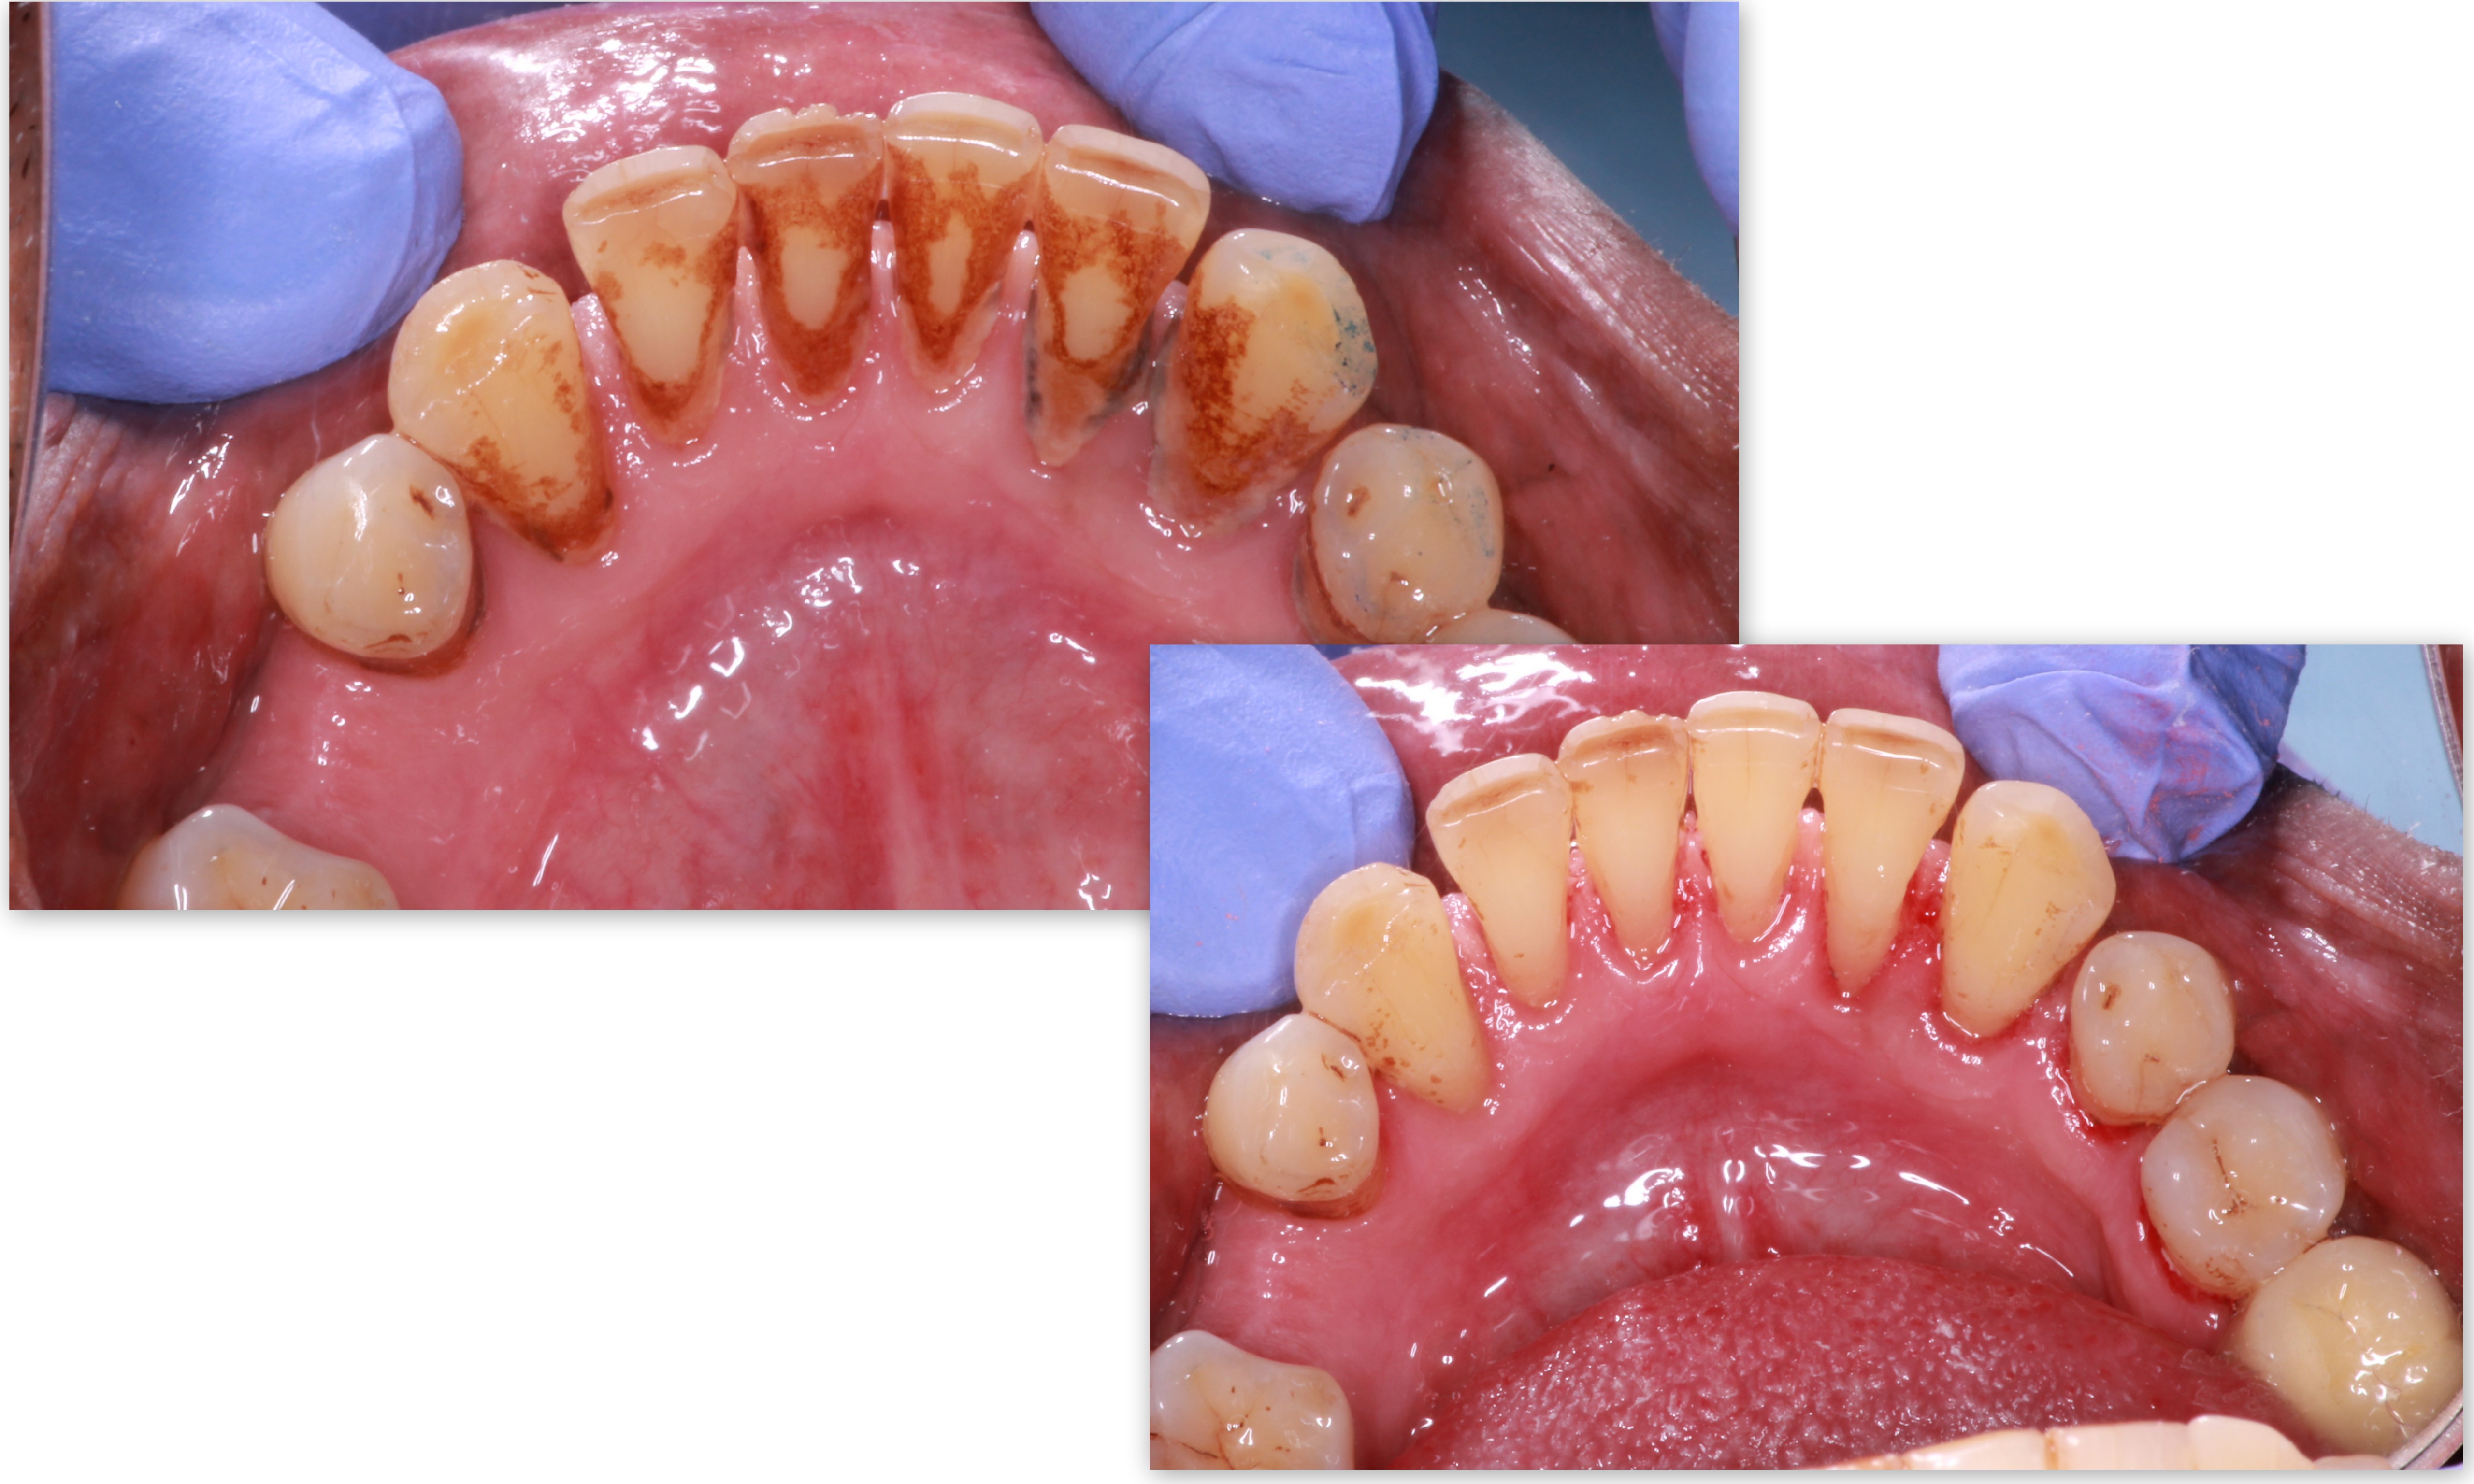

Oral prophylaxis means tooth cleaning by your dentist and is a mandatory dental procedure to be done every 6 months. It is highly recommended for those patients who have extrinsic stains due to smoking tobacco, betel nut chewing etc, who have tartar accumulation due to unwanted food particles which leads to bad breath - a common complain of a patient and in cases of bleeding gums and infections.

The procedure usually requires only one office visit. But two or three sessions can be required varying from case to case. The dentist will use an ultrasonic cleaning tip in all the areas where the tooth brush can't reach. The vibration makes the tartar and stains loosen off from the teeth and gums. Polishing is done to get a sparkle in your teeth after cleaning is done.